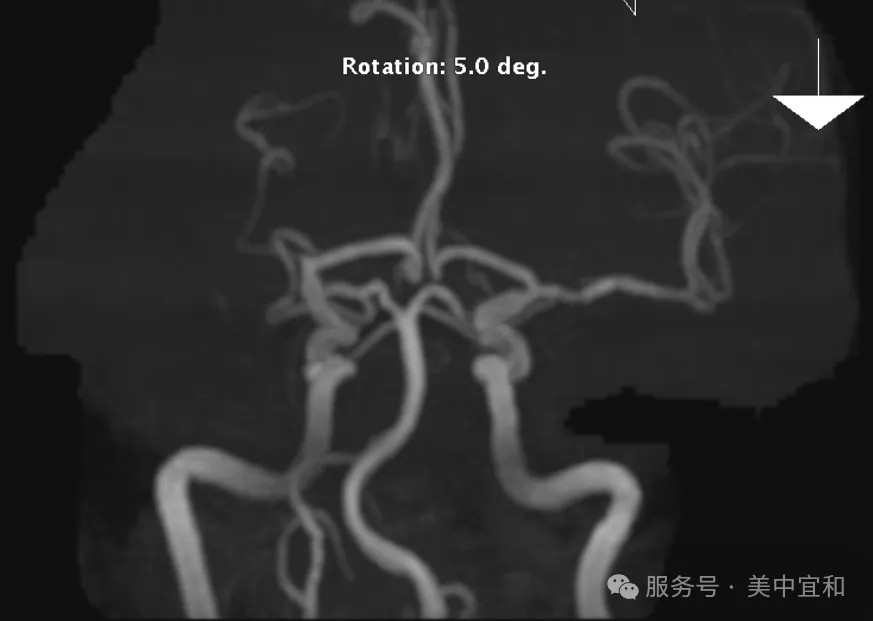

春回大地、万物复苏,像所有备孕夫妻一样,T女士(化名)一家对迎接一个新生命充满了期待,但她的备孕之旅却在启程阶段显得有些举棋不定,3年前一次头颅核磁检查提示“双侧颈内动

冠状动脉和右侧大脑中动脉的双重警报

近日,北京宜和医院心内科收治了一位72岁的高龄男性患者。他有长达16年的冠心病史,曾多次接受冠脉介入治疗(PCI)。近两个月来,反复出现胸闷、心悸等不适症状,尽管已在其他医院接受过支架植入和药物球囊扩张等处理,但症状仍未得到有效缓解,严重影响生活质量。为求进一步诊治,患者来到心内科。